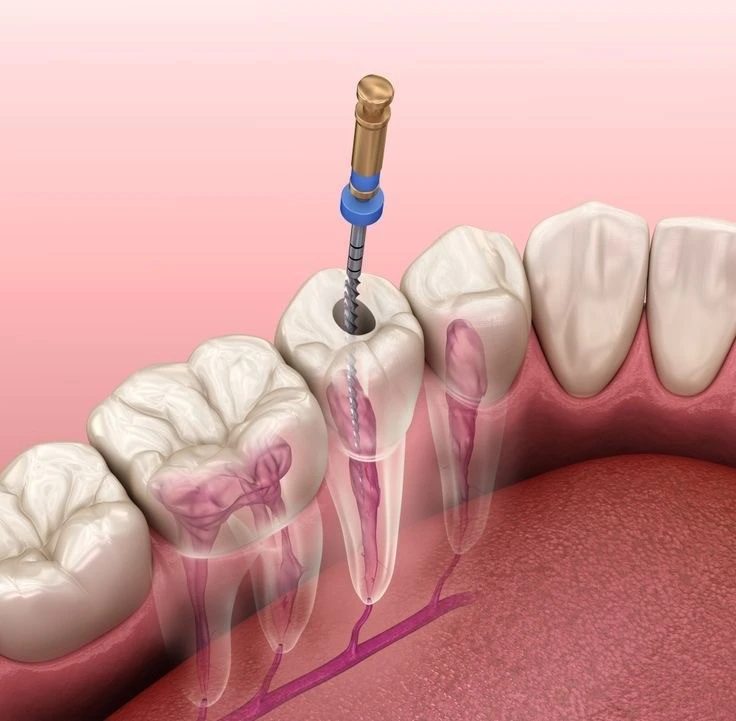

Procedura gde se ručnom ili mašinskom instrumentacijom uklanja živac (pulpa) zuba koje ima za cilj ozdravljenje zuba. Situacija koja dovode zub u to stanje je uznapredovala karijesna lezija.

Postupak ove procedure je:.

-Vadjenje živca predstavlja prvu faza u lečenju zuba, podrazumeva fizičko uklanjanje zubne pulpe (živca) i svog infektivnog sadržaja iz kanala korena zuba, pod dejstvom lokalne anestezije.

-Obrada kanala korena je druga faza u lečenju zuba i podrazumeva oblikovanje kanala korena zuba posebnim ručnim ili mašinskim instrumentima, sa ciljem da se ukloni zaostalo inficirano tkivo zubne pulpe (živca).

-Punjenje kanala korena zuba je poslednja faza i podrazumeva ispunjavanje pripremljenog i oblikovanog kanala. Primena gutaperka kočićima i pastama koje se vežu unutar oblikovanog kanala i na taj način štite i čuvaju zub od daljih mogućih infekcija.